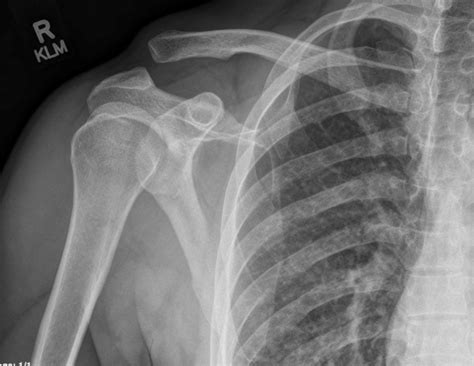

An Ac Joint X Ray is a diagnostic imaging technique used to visualize the acromioclavicular joint. This type of X-ray provides detailed images of the bones and the surrounding structures, helping healthcare professionals to diagnose injuries, fractures, or other abnormalities in the AC joint. The procedure is non-invasive and relatively quick, making it a preferred method for initial assessments of shoulder pain.

Interpreting the results of an Ac Joint X Ray requires a trained eye. Radiologists look for specific signs and abnormalities that indicate various conditions. Here are some key points they consider:

• Joint Space: The space between the clavicle and scapula should be uniform. Any narrowing or widening can indicate injury or degeneration.

• Bone Alignment: The bones should be properly aligned. Any displacement or misalignment can suggest a fracture or dislocation.